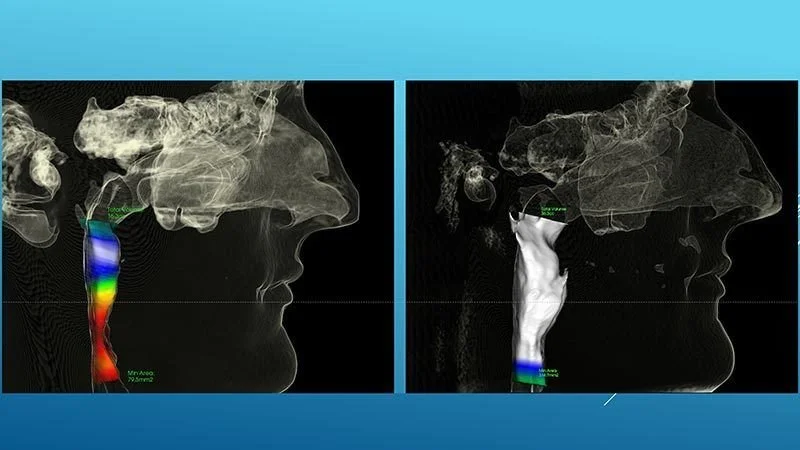

Before & After ALF Treatment on a 30-year-old man:

Anxiety, fear, trouble swallowing and extreme difficulty with social interaction were just a few of the chief concerns of this oxygen-deprived 30-year-old man. Following two years of ALF therapy with the ALF Educational Institute (AEI), the tremendous growth of his airway (red to white) is observed. More than that is the complete absence of all symptoms reported initially. This is a brain on oxygen! No CPAP or intraoral sleep and snore management methods are necessary once the body has transformed the actual architecture that caused the problems in the first place.